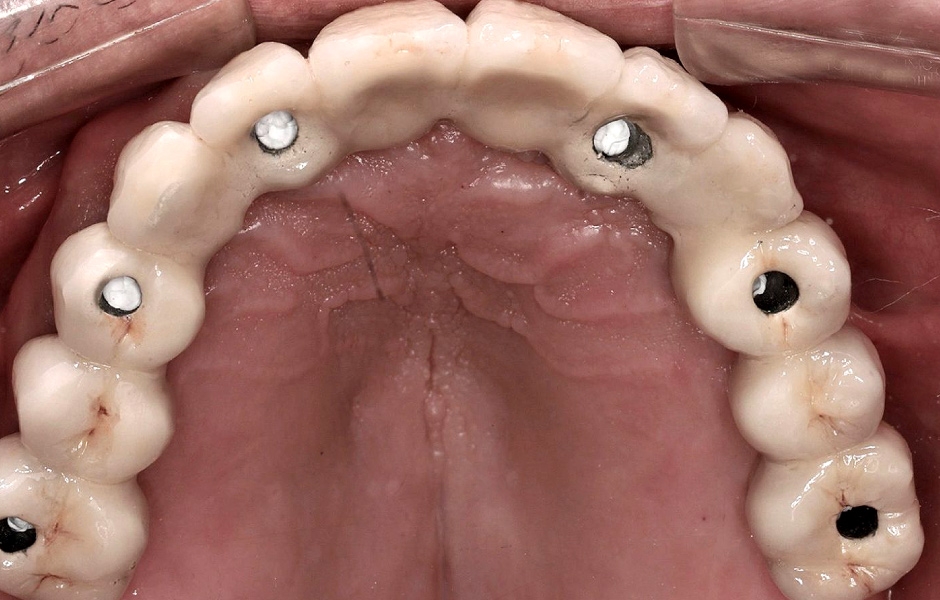

Při další návštěvě byly vyfrézovaný prototyp náhrady a verifikační šablona vyzkoušeny v ústech a následně byl dokončen návrh a výroba definitivní náhrady (obr. 47, 48).

Pro kotvení definitivní náhrady byly použity abutmenty Variobase® for Bridge. Materiálem pro výrobu definitivní náhrady byl zvolen monolitický zirkon (obr. 49, 50).

Obr. 47

Obr. 48

Obr. 49

Obr. 50